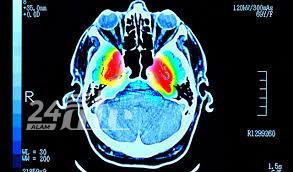

استطاع مجموعة من العلماء والباحثين في جامعة جنوب كاليفورنيا (USC) من التوصّل إلى اكتشاف علمي مهم قد يكون له تأثير بالغ في التشخيص المبكر لأمراض الدماغ، خاصة مرض ألزهايمر. حيث نُشرت دراسة جديدة في دورية Nature Cardiovascular Research، بيّنت أنه تم رصد ما عُرف بـ”النبض الخفي” للأوعية الدموية الدقيقة داخل الدماغ، وهو اكتشاف يمكن أن يساعد في فهم أفضل للشيخوخة والأمراض العصبية.

الدراسة قدمت طريقة غير جراحية لقياس التغيرات الدقيقة في حجم الأوعية الدموية باستخدام تقنية “التصوير بالرنين المغناطيسي فائق الدقة (7 تسلا)”. وبحسب النتائج فإنّ هذه النبضات تتزايد مع تقدم العمر، ووجود عوامل خطر، مثل ارتفاع ضغط الدم. وتظهر هذه التغيرات بشكل خاص في “المادة البيضاء العميقة في الدماغ”، ووالتي تلعب دورًا حيويًا في نقل الإشارات العصبية.

وقد اعتمدت الدراسة في قياس التغيرات التي تطرأ بشكل طفيف على حجم الأوعية أثناء دورة القلب، اعتمدت على الجمع بين اثنتين من أحدث التقنيات، هما VASO وASL. وقد لاحظ الباحثون أن المتقدمين في العمر، وبالأخص أولئك الذين يعانون من ارتفاع ضغط الدم، تكون لديهم النبضات الوعائية أقوى، ما قد يسبب ضررًا لأنظمة تنقية الدماغ.